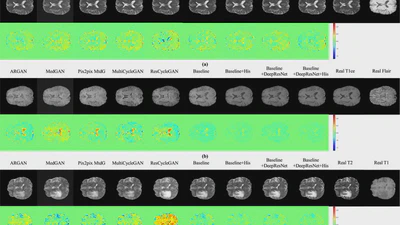

(2023). A histogram-driven generative adversarial network for brain MRI to CT synthesis. Knowledge-Based Systems.